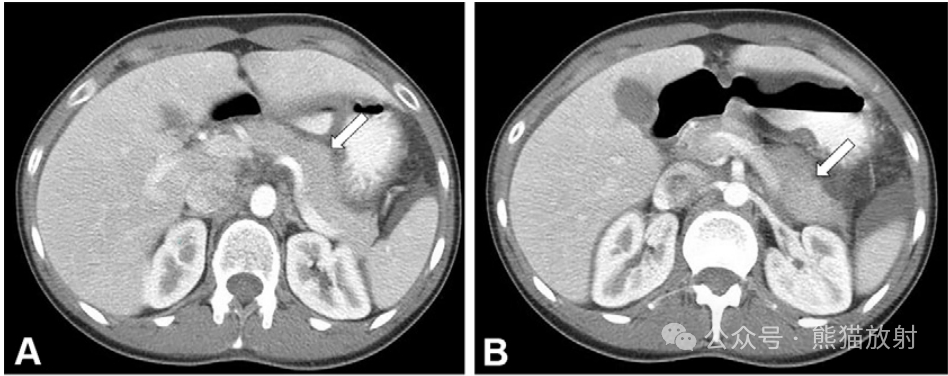

28岁女性,异位胰腺并发急性胰腺炎,伴有腹痛恶心(血清脂肪酶水平升高至1300U/L)。轴位增强CT图像显示正常原位胰腺,无炎症证据(A、B中的白箭)。胃窦可见一外生性分叶状肿块(C-F中的白箭头),与原位胰腺外观和增强相似,周围脂肪间隙浑浊。还注意其中心有一个原始管状结构(C、D中的黑箭)。